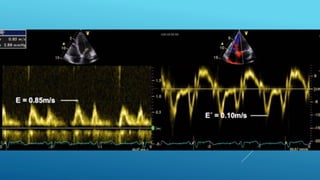

โ€ข Tricuspid annular plane systolic excursion

โ€ข TAPSE of <17 mm indicates RV dysfunction

โ€ข Tricuspid annular systolic velocity

โ€ข Tissue Doppler of the free lateral wall

โ€ข An Sโ€™ value < 9.5 cm/s should raise the suspicion for abnormal RV function